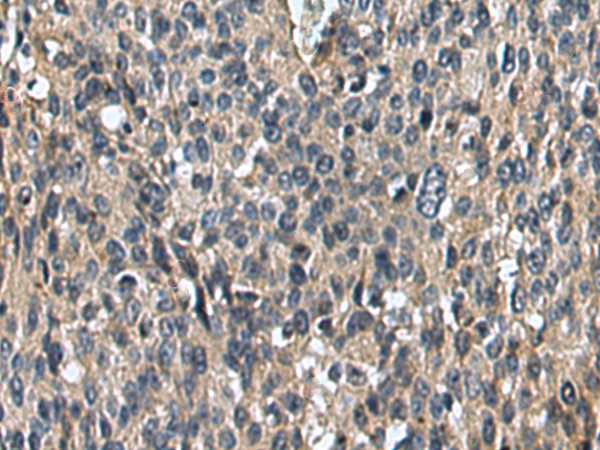

IHC positive control: |

Human ovarian cancer and Human colorectal cancer |